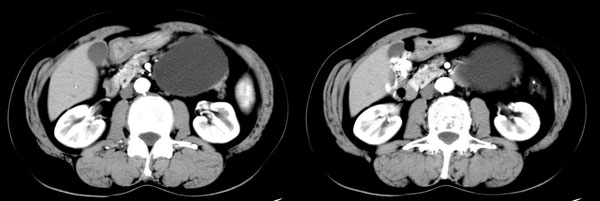

女性,58岁。卵巢癌术后4年余,无不适。体检b超发现左上腹肿块。

ct平扫加增强扫描:胆囊折叠,壁厚,其内见结石。胰腺体尾部见一5.8x7.5cm囊性肿物,ct值12hu,壁薄,增强扫描未明显强化,胰头不大,强化均匀。